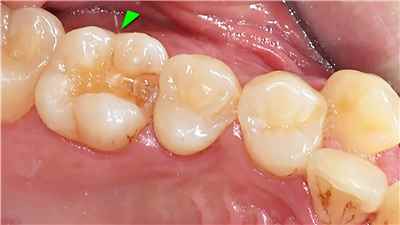

치아 변색 외부 요인